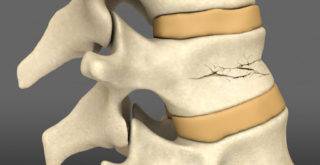

Вертебропластика, или кифопластика позвоночника, как ее еще называют — операция, при которой происходит восстановление позвоночной костной ткани. Хирургическое вмешательство показано пациентам, перенесшим компрессионный перелом позвоночника. При травмах такого рода целостность позвонков теряется по причине их сдавливания и одновременного сгибания.

Часто переломы компрессионного типа возникают по причине локализации сопутствующего недуга — остеопороза. Болезнь разрушает костные ткани, делая их хрупкими и ломкими. На фоне таких симптомов, травмы локализуются намного легче, чем у здоровых людей.

Остеопороз – наиболее частое заболевание, при котором происходят патологические переломы тел позвонков. Человеку с этим диагнозом достаточно оступиться или даже кашлянуть.